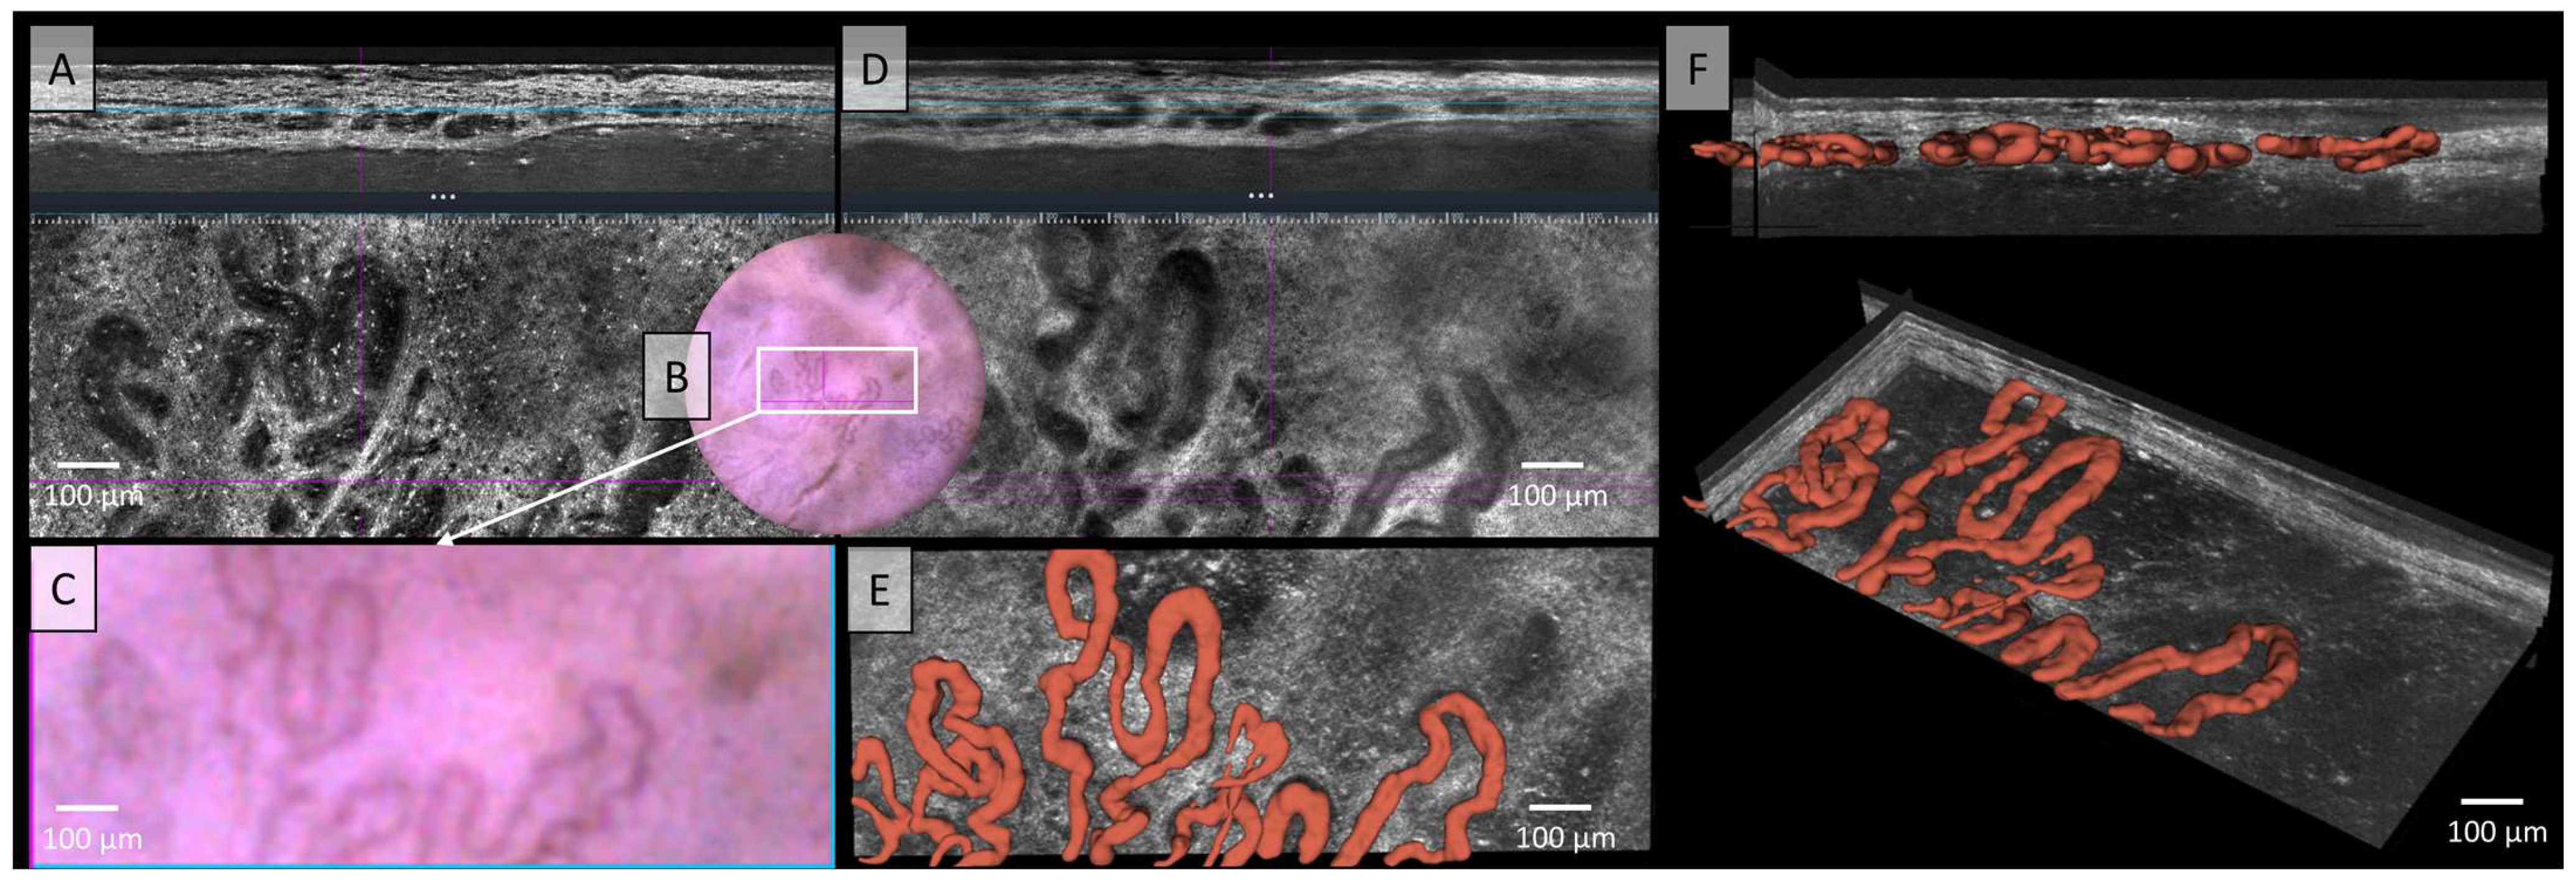

The LC-OCT image in Figure 5 shows irregular, tortuous, twisted, and dilated vessels in both vertical and horizontal sections, which can also be recognised in dermoscopy. In standard LC-OCT, the plasticity of the vessels can only be assumed by viewing both vertical and horizontal slices together. Neither static LC-OCT nor dermoscopy can clearly show whether the vessels cross above or below each other. Moving images in LC-OCT can solve this problem, but still cannot visualize full plasticity. The problem of representing vessel plasticity in space using conventional LC-OCT, already described in the previous section, was solved in Figure 5E,F through by the 3D reconstruction of the vessels, which clearly displays the spatial relationships between the vessels. Furthermore, not only intersecting vessels can be clearly displayed, but also the exact plane in which the vessels are located can be analyzed. The example of this basal cell carcinoma (BCC) clearly shows that the vessels are mostly connected, elongated, sinuous, partly hairpin-like vessels, which are very impressive in terms of caliber. A very strong blood flow with marginal leukocyte rolling can also be visualised in the moving image or video recordings (see Video S2).

Figure 5.

Vessels of a basal cell carcinoma (BCC) in Line field confocal optical coherence tomography (LC-OCT); (A) Normal rendering (deepGaussian) shows an irregular, tortuous vascular morphology with twisted and dilated vessels in both vertical (top image, LC-OCT image size: 1.2 mm (width) × 0.4 mm (height)) and horizontal section (middle image, LC-OCT image size: 1.2 mm (width) × 0.5 mm (height)), zoom on integrated LC-OCT dermoscopy ((B,C) bottom image, image size: 1.2 mm (width) × 0.5 mm (height)) shows the same; the white rectangle represents the area of taken LC-OCT scan. (D) Minimum rendering with large vessel thickness on (top and middle image). (E) Horizontal view of three-dimensional (3D) visualisation shows multiple, mostly connected, elongated, sinuous, partly hairpin-like vessels, which are very impressive in terms of caliber (red) (bottom image, LC-OCT image size: 1.2 mm (width) × 0.5 mm (height)); (F) two different perspectives of the 3D reconstruction show that the vessels are primarily arranged in one plane (LC-OCT images size: 1.2 (width) × 0.5 (length) × 0.5 (height) mm3).

In Figure 5, hairpin vessels were already visible in dermoscopy, and these were subsequently identified in the dermis using LC-OCT. According to the literature, this vascular morphology is observed in both melanocytic and non-melanocytic tumors, and occasionally even in benign skin lesions [44,45]. In Figure 5, these vessels were depicted in direct association with the nodular tumor nests of a nodular BCC, a finding previously described by Lupu et al. using RCM [46]. Notably, thick, large-caliber vessels, as seen in our case, are well-documented in the literature. Braun et al. describe thick, branching arborizing vessels that taper towards the periphery, while Lupu et al. reported hairpin vessels in 66.7% of cases involving aggressive BCCs of the lower extremities [46,47]. This is consistent with our findings, as the patient’s pigmented nodular BCC was located on the extensor surface of the lower leg. Ulrich et al. also described the blood vessels surrounding tumor nests in BCCs. Their studies report the presence of both very thick and very thin vessels. Similarly, our LC-OCT 3D reconstruction, as previously described, also reveals both very thick and very thin vessels. However, due to the limited examination area in our study, we cannot determine whether the vessels are primarily localized in the center, as noted in their work [18].